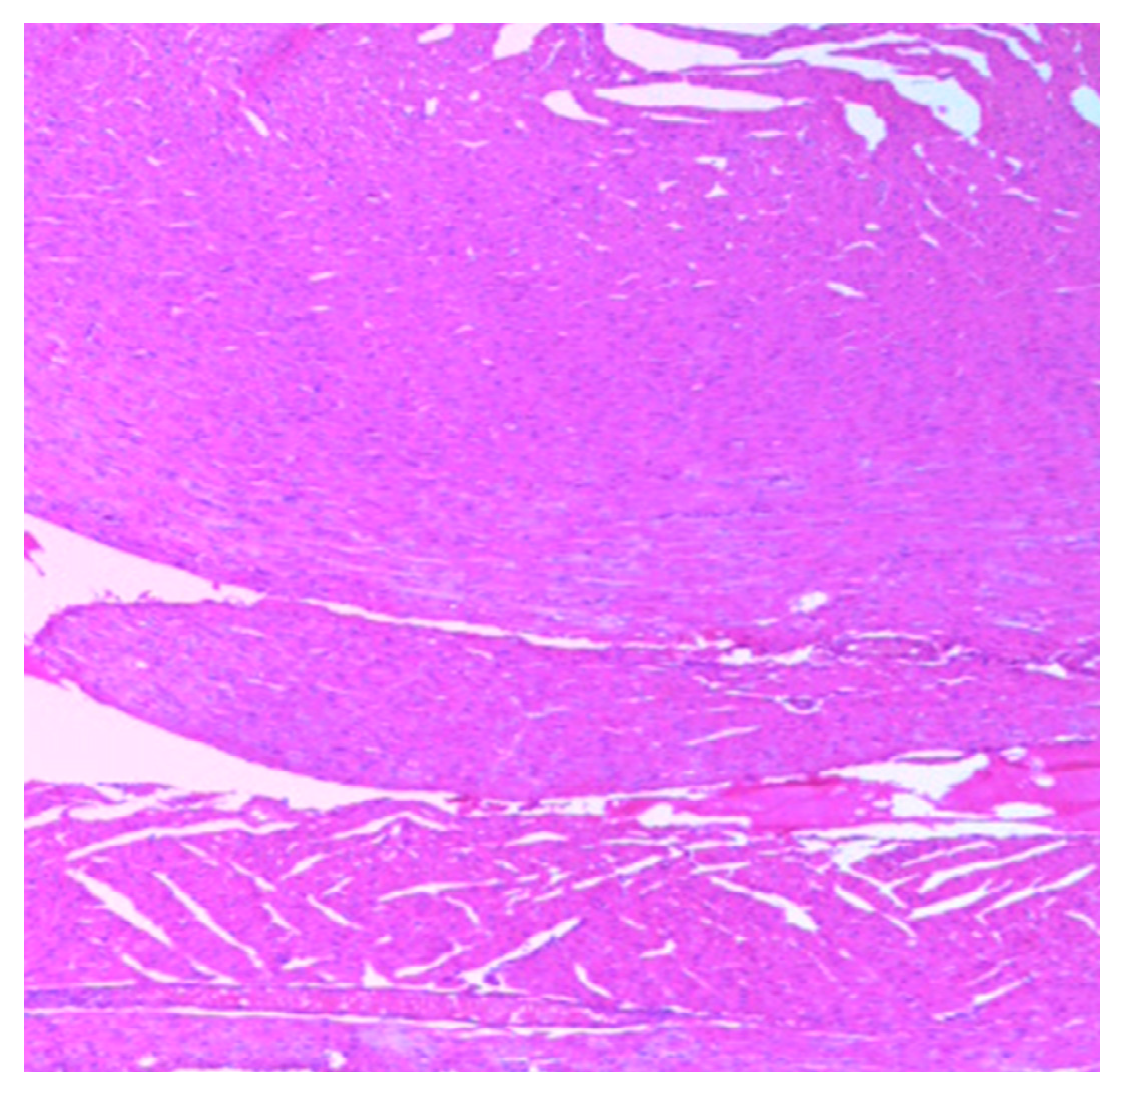

The histology of the hearts of the rat models examined is shown in Figure 13, Figure 14, Figure 15, Figure 16 and Figure 17. Gestation had no histological changes in the cardiac tissues (Figure 14 and Figure 15), while clay beverage consumption during both early and late gestation caused inflammation (Figure 16) and necrosis (Figure 17) of cardiac tissues. We deduce that the functional integrity of the cardiovascular system is at risk during gestation if clay beverage is part of nonfood substances frequently consumed.

Figure 13.

Histopathologic slide of the heart muscle of control rats showing no obvious atypical or reactive change in histology.

Figure 14.

Histopathologic slide of the heart muscle of rats during early gestation stage showing no obvious atypical or reactive change in histology.

Figure 15.

Histopathologic slide of the heart muscle of rats during late gestation stage showing no obvious atypical or reactive change in histology.

Figure 16.

Histopathologic slide of the heart muscle of rats administered clay beverage during early gestation stage showing mild inflammation.

Figure 17.

Histopathologic slide of the heart muscle of rats administered clay beverage during late gestation stage showing inflammation and necrosis.